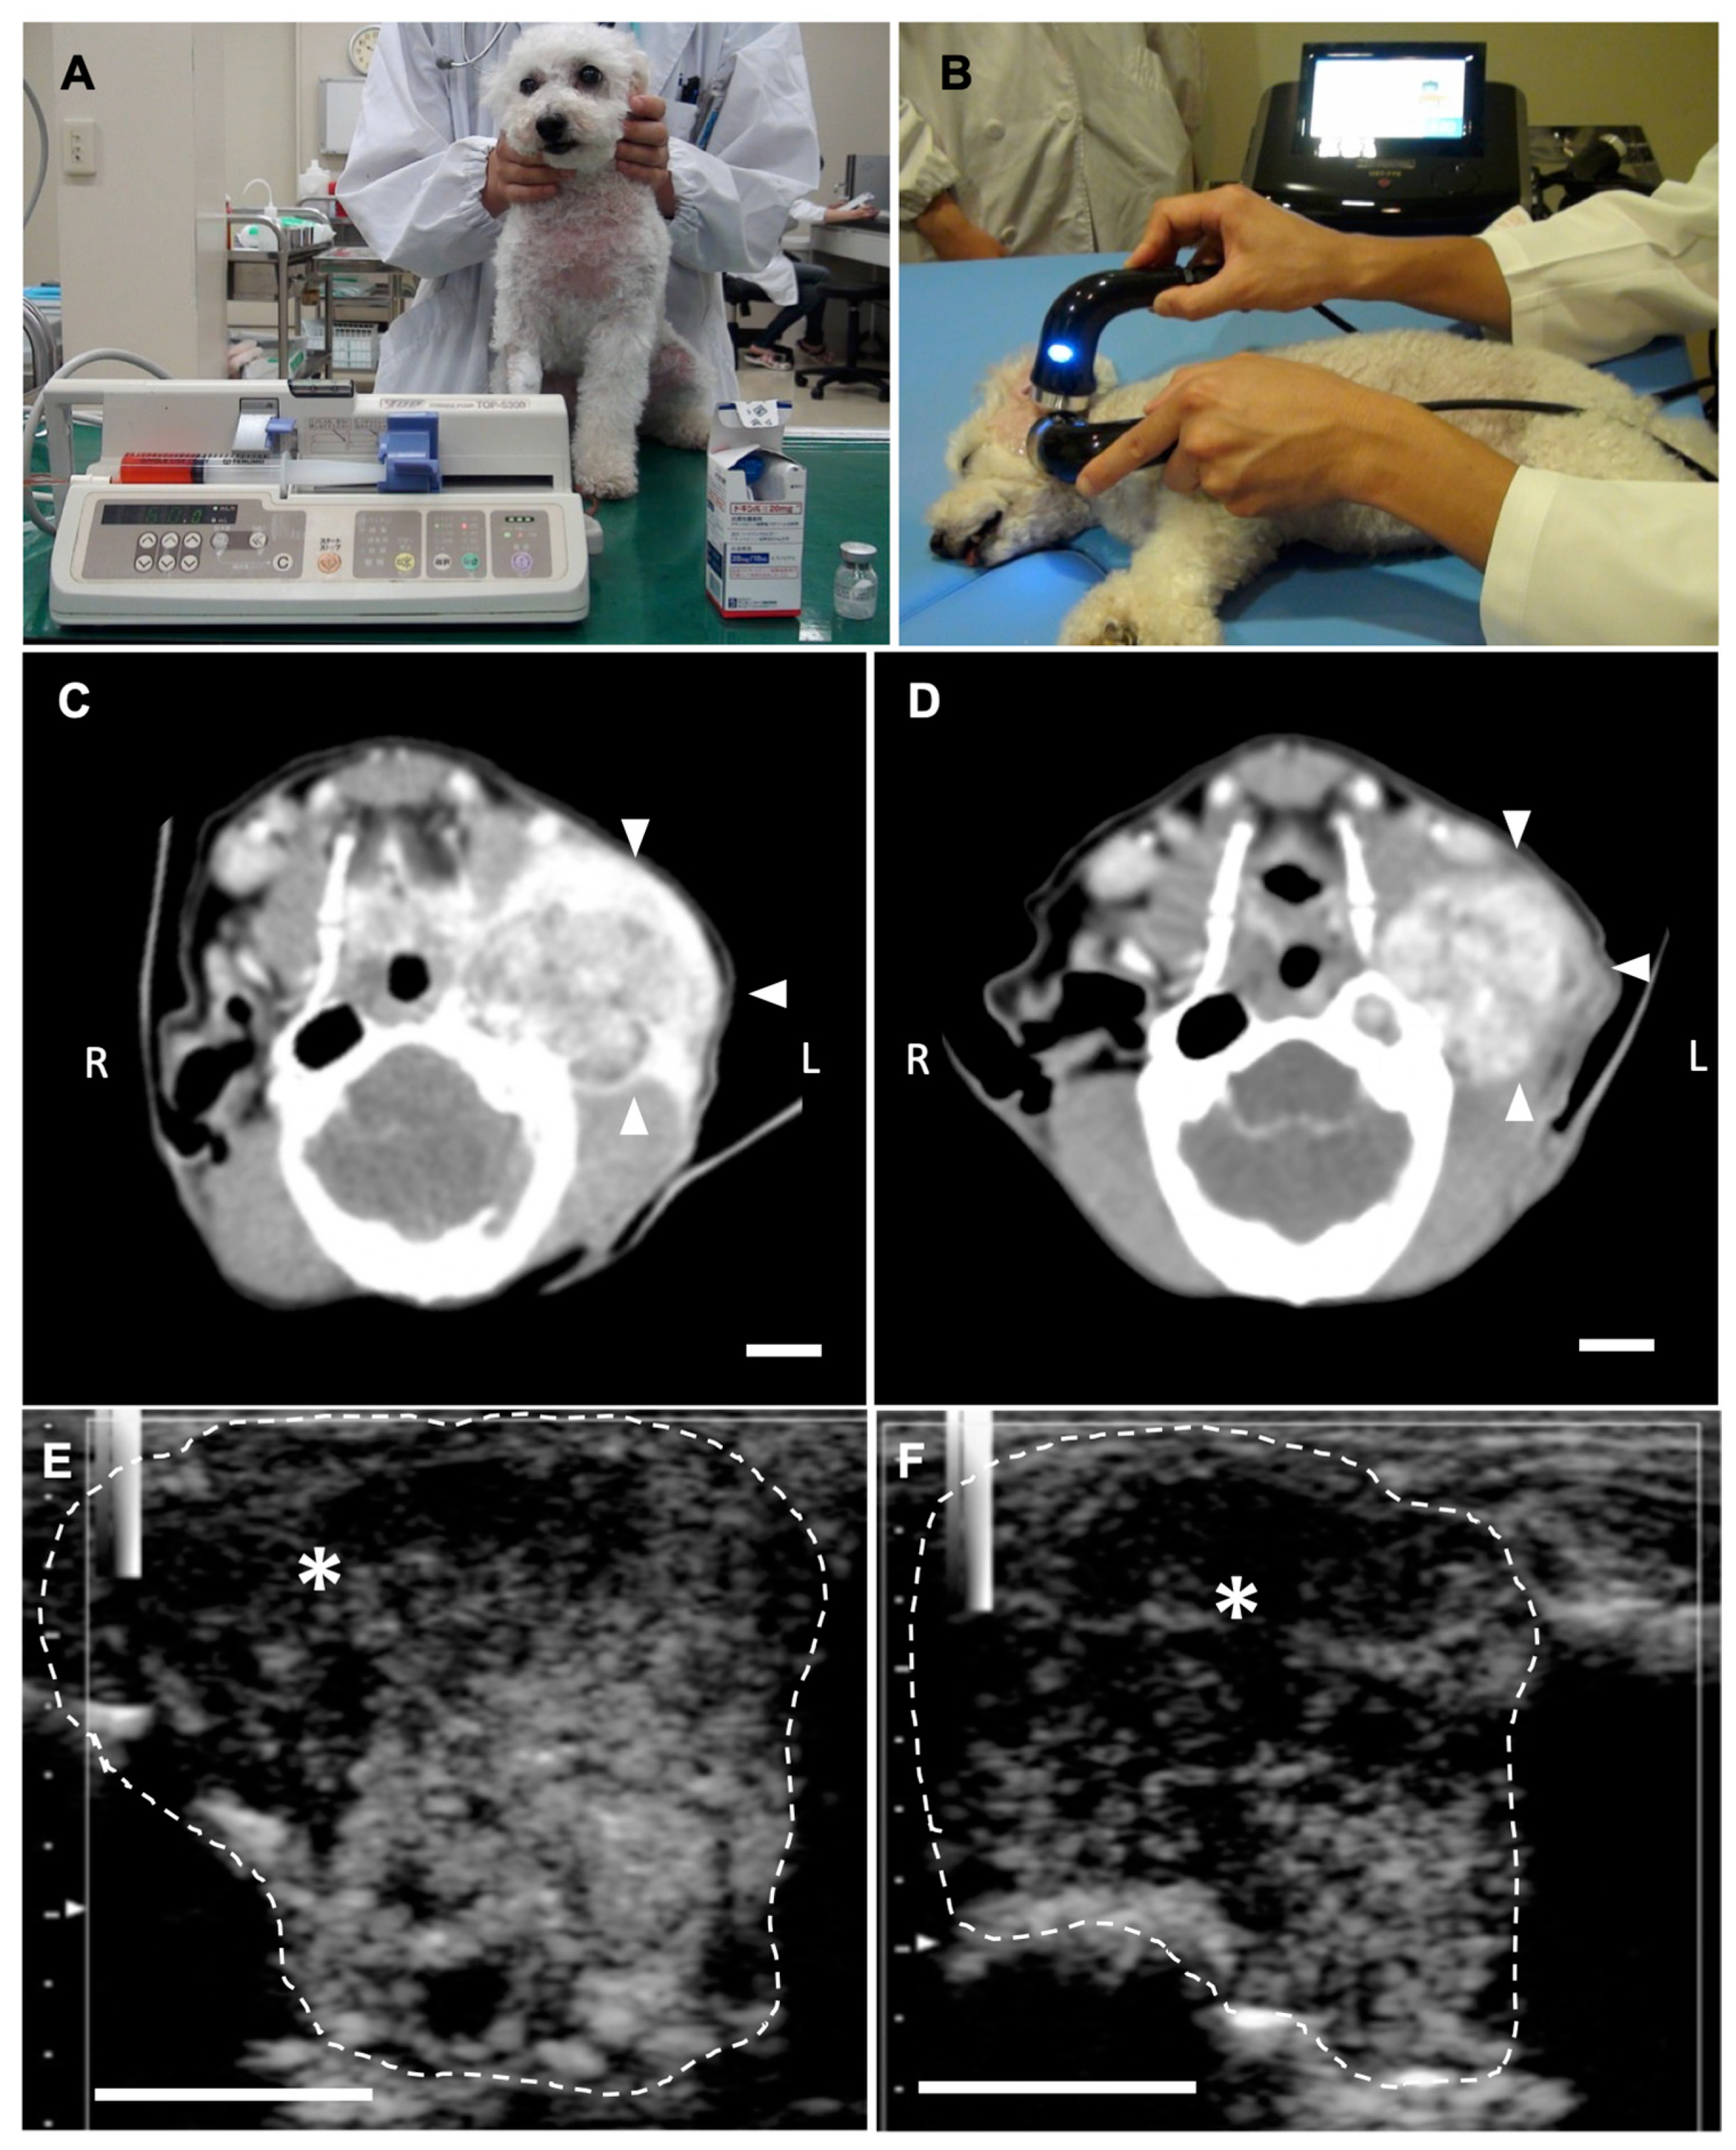

2.3. Anti-Tumor Effects of LBs in Combination with Therapeutic US and Liposomal Doxorubicin

4.4.1. Animals

4.4.2. Treatment Protocol

4.4.3. CEUS for the Assessment of Tumor Vasculature

4.4.4. Measurement of Tumor Size